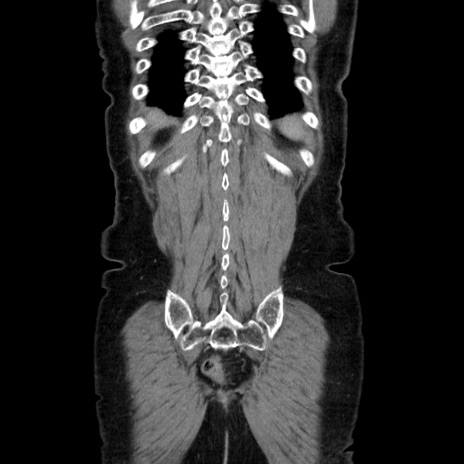

症例5(冠状断像)

【症例】70歳代女性

【主訴】お腹が張る

【現病歴】1週間くらい前から腹部膨満の自覚あり。昨日夜から増悪したため、本日救急外来受診。

【身体所見】意識清明、BT 36.5℃、BP 165/106mmHg、HR 80bpm、SpO2 98%、腹部:膨満、軟、自発痛・圧痛なし、触診にて不快感あり、腸蠕動音:減弱

【データ】WBC 12600、CRP 1.04